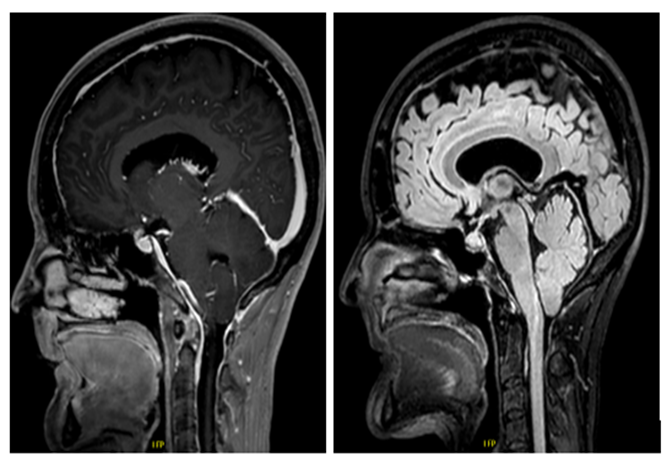

Brain MRI (Figure 1) revealed:

• Meningeal enhancement in the posterior fossa

• Caudal descent of cerebellar tonsils <5 mm, without evidence of brainstem compression against the foramen magnum.

• Periventricular white matter changes (suggestive of chronic microangiopathy)

Figure 1: Radiological signs of intracranial hypotension with appearance of pachy-meningitis especially at the posterior fossa and pseudo-chiari with the tonsils in a fairly low position.